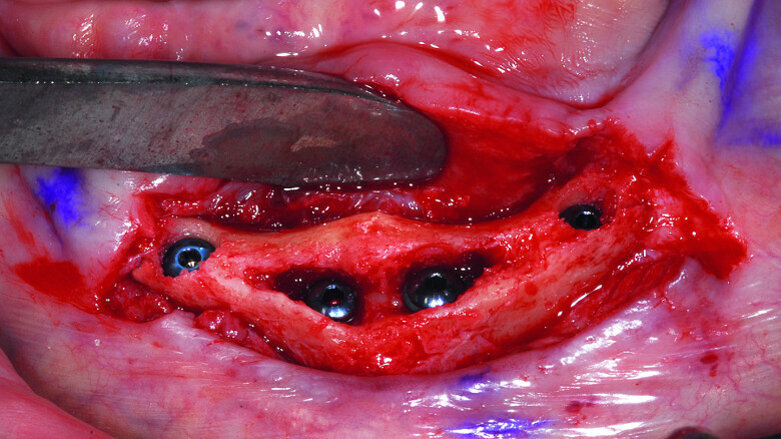

Fig. 13: A full thickness mucoperiosteal flap exposed the knifeedged ridge of the mandibular symphysis.

Based on the CBCT data and interactive treatment planning simulations, it was elected to complete the surgical placement of four implants in the anterior symphysis in a ‘diagnostic-freehand’ manner. The anatomical landmarks were clear and allowed the accuracy of implant positioning. The knife-edged ridge required a full flap surgical approach (Fig. 13).

The broken drill was immediately located lingual to the alveolar crest embedded in the soft tissue. Apparently, the drill deflected off the sharp ridge into the floor of the mouth, and the torque caused the drill to break. Fortunately, the drill did not cause any immediate complications as the floor of the mouth contains many vessels, which if perforated, could have resulted in a sublingual hematoma. The remaining broken drill as seen in Figure 14 was easily retrieved.

Once the offending element was removed, the plan was to reduce the knife-edged ridge to gain appropriate width for implant placement. The reduction was accomplished in a free-hand method based upon the position and location of the mental foramen on either side of the symphysis. Based upon a thorough review of the CBCT scan data the expected hollow area of bone in the anterior symphysis was exposed (Fig. 15).

Prior to implant placement, the soft tissue in the anterior symphysis was carefully removed with serrated curettes and serrated round burs. Following the simulated plan, osteotomies were prepared for four implants to support an overdenture. The two middle implants were 4.0 mm diameter by 13 mm in length, and the two distal implants were 3.5 mm by 13 mm in length approximately 1–2 mm below the bone crest as per manufacturer’s protocol (AnyRidge, MegaGen Implants). Each implant was well fixated due to three factors: (1) the anticipated thickness of the buccal and lingual cortical plates; (2) the apical length of the implants engaging native bone; and (3) the thread design of the implant type (Figs. 16a & b).